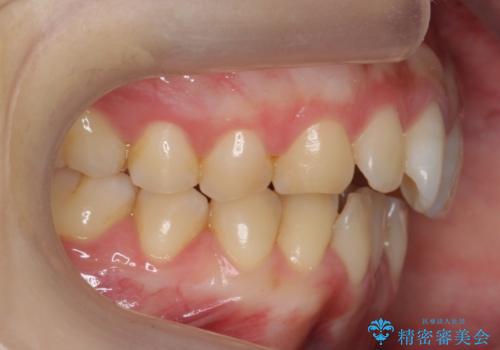

前歯のガタつき インビザラインで 下の前歯を1本抜歯

- 前歯のがたつきを主訴に来院。マウスピース矯正を希望されました。

治療にあたり、下の前歯を一本抜歯しています。

非抜歯で無理に治療をしようとすると、下の前歯の骨が薄く歯ぐきが下がったり、歯がぐらついたり、がたつきが完全にとれないリスクがあることを説明しました。

下の前歯が3本になるため、上下の正中は合わない仕上がりとなりますが、正中を合わせるには上下左右4本抜歯の上、ワイヤー矯正となってしまいます。

それよりは抜歯の数も少なく、メリットが大きいのではないかと説明し、選んでいただきました。

短期間できれいな歯並びになり、大変満足していただきました。